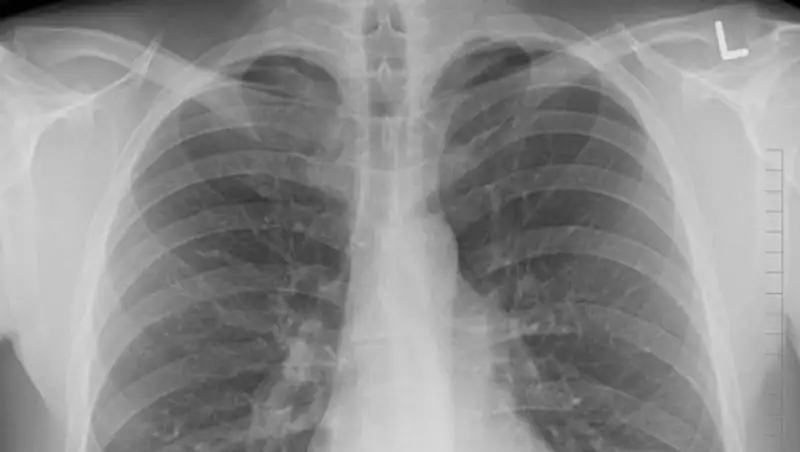

В Казахстане за сутки 353 человека заболели пневмонией, сообщает zakon.kz.

1 случай с летальным исходом. За сутки выздоровели 37 человек, - сообщили в министерстве здравоохранения.

С 1 - 11 сентября 2020 г. зарегистрировано: заболевших- 28 928, случаев с летальным исходом - 318, всего выздоровели – 6642 человек.